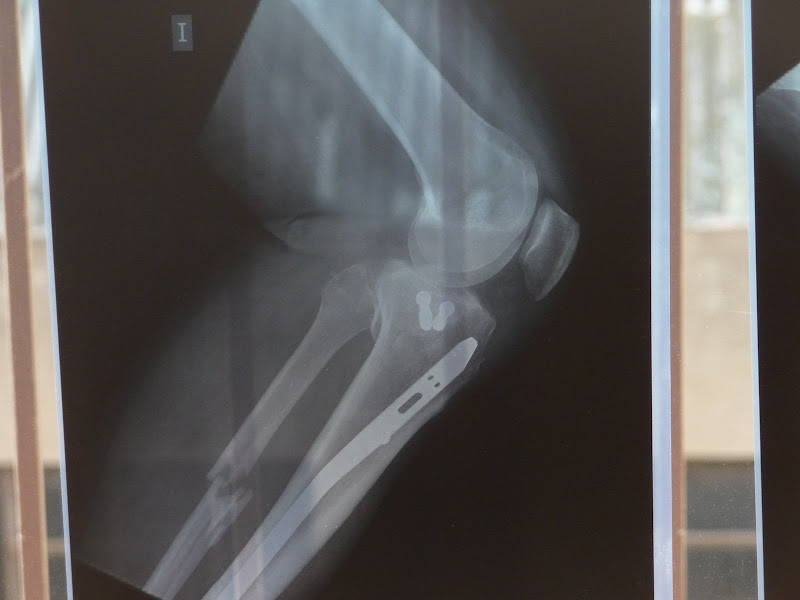

Doncs de moment bé. Jo vaig movent cada cop mes la cama, i l'Esther cada dia mes cansada de cuidar-me, jeje. Avui hem anar a veure el metge, m'han fet unes radiografies (que he aprofitat per fer unes fotos) i diu que tot va molt be, que si segueix aixi, a finals d'abril podre posar el peu a terra.

Sergi3 ha escrit:........ m'han fet unes radiografies (que he aprofitat per fer unes fotos) ............

NO FOTOS= NO RADIOGRAFIA :mestre

Randy-650 ha escrit:

Ale, si foto=si radiografia :D

Aixo ho arreglen com qui posa 4 cargols per arreglar un armari

Imatge

Ostres que xules, jo vull un ferro així !!!!

Auughh!! M'ha fet mal a mi i tot de veure-les.

Deu ni dò. I aquest peronè? tot sol ja es posarà a lloc?

A mi també en fa mal només de veure-ho. :shock:

Sort que en sergi és un HOME de veritat, no com molts de nosaltres que només ho semblem. :!:

Amb aquesta trencada i no va dir practicament ni piu, és un HOME de dalt a baix. :wink:

Vendetta ha escrit:Deu ni dò. I aquest peronè? tot sol ja es posarà a lloc?

Aixó diu el metge, i que si no no passa res, pero jo no les tinc totes. Ell ni li va donar gaire importancia.